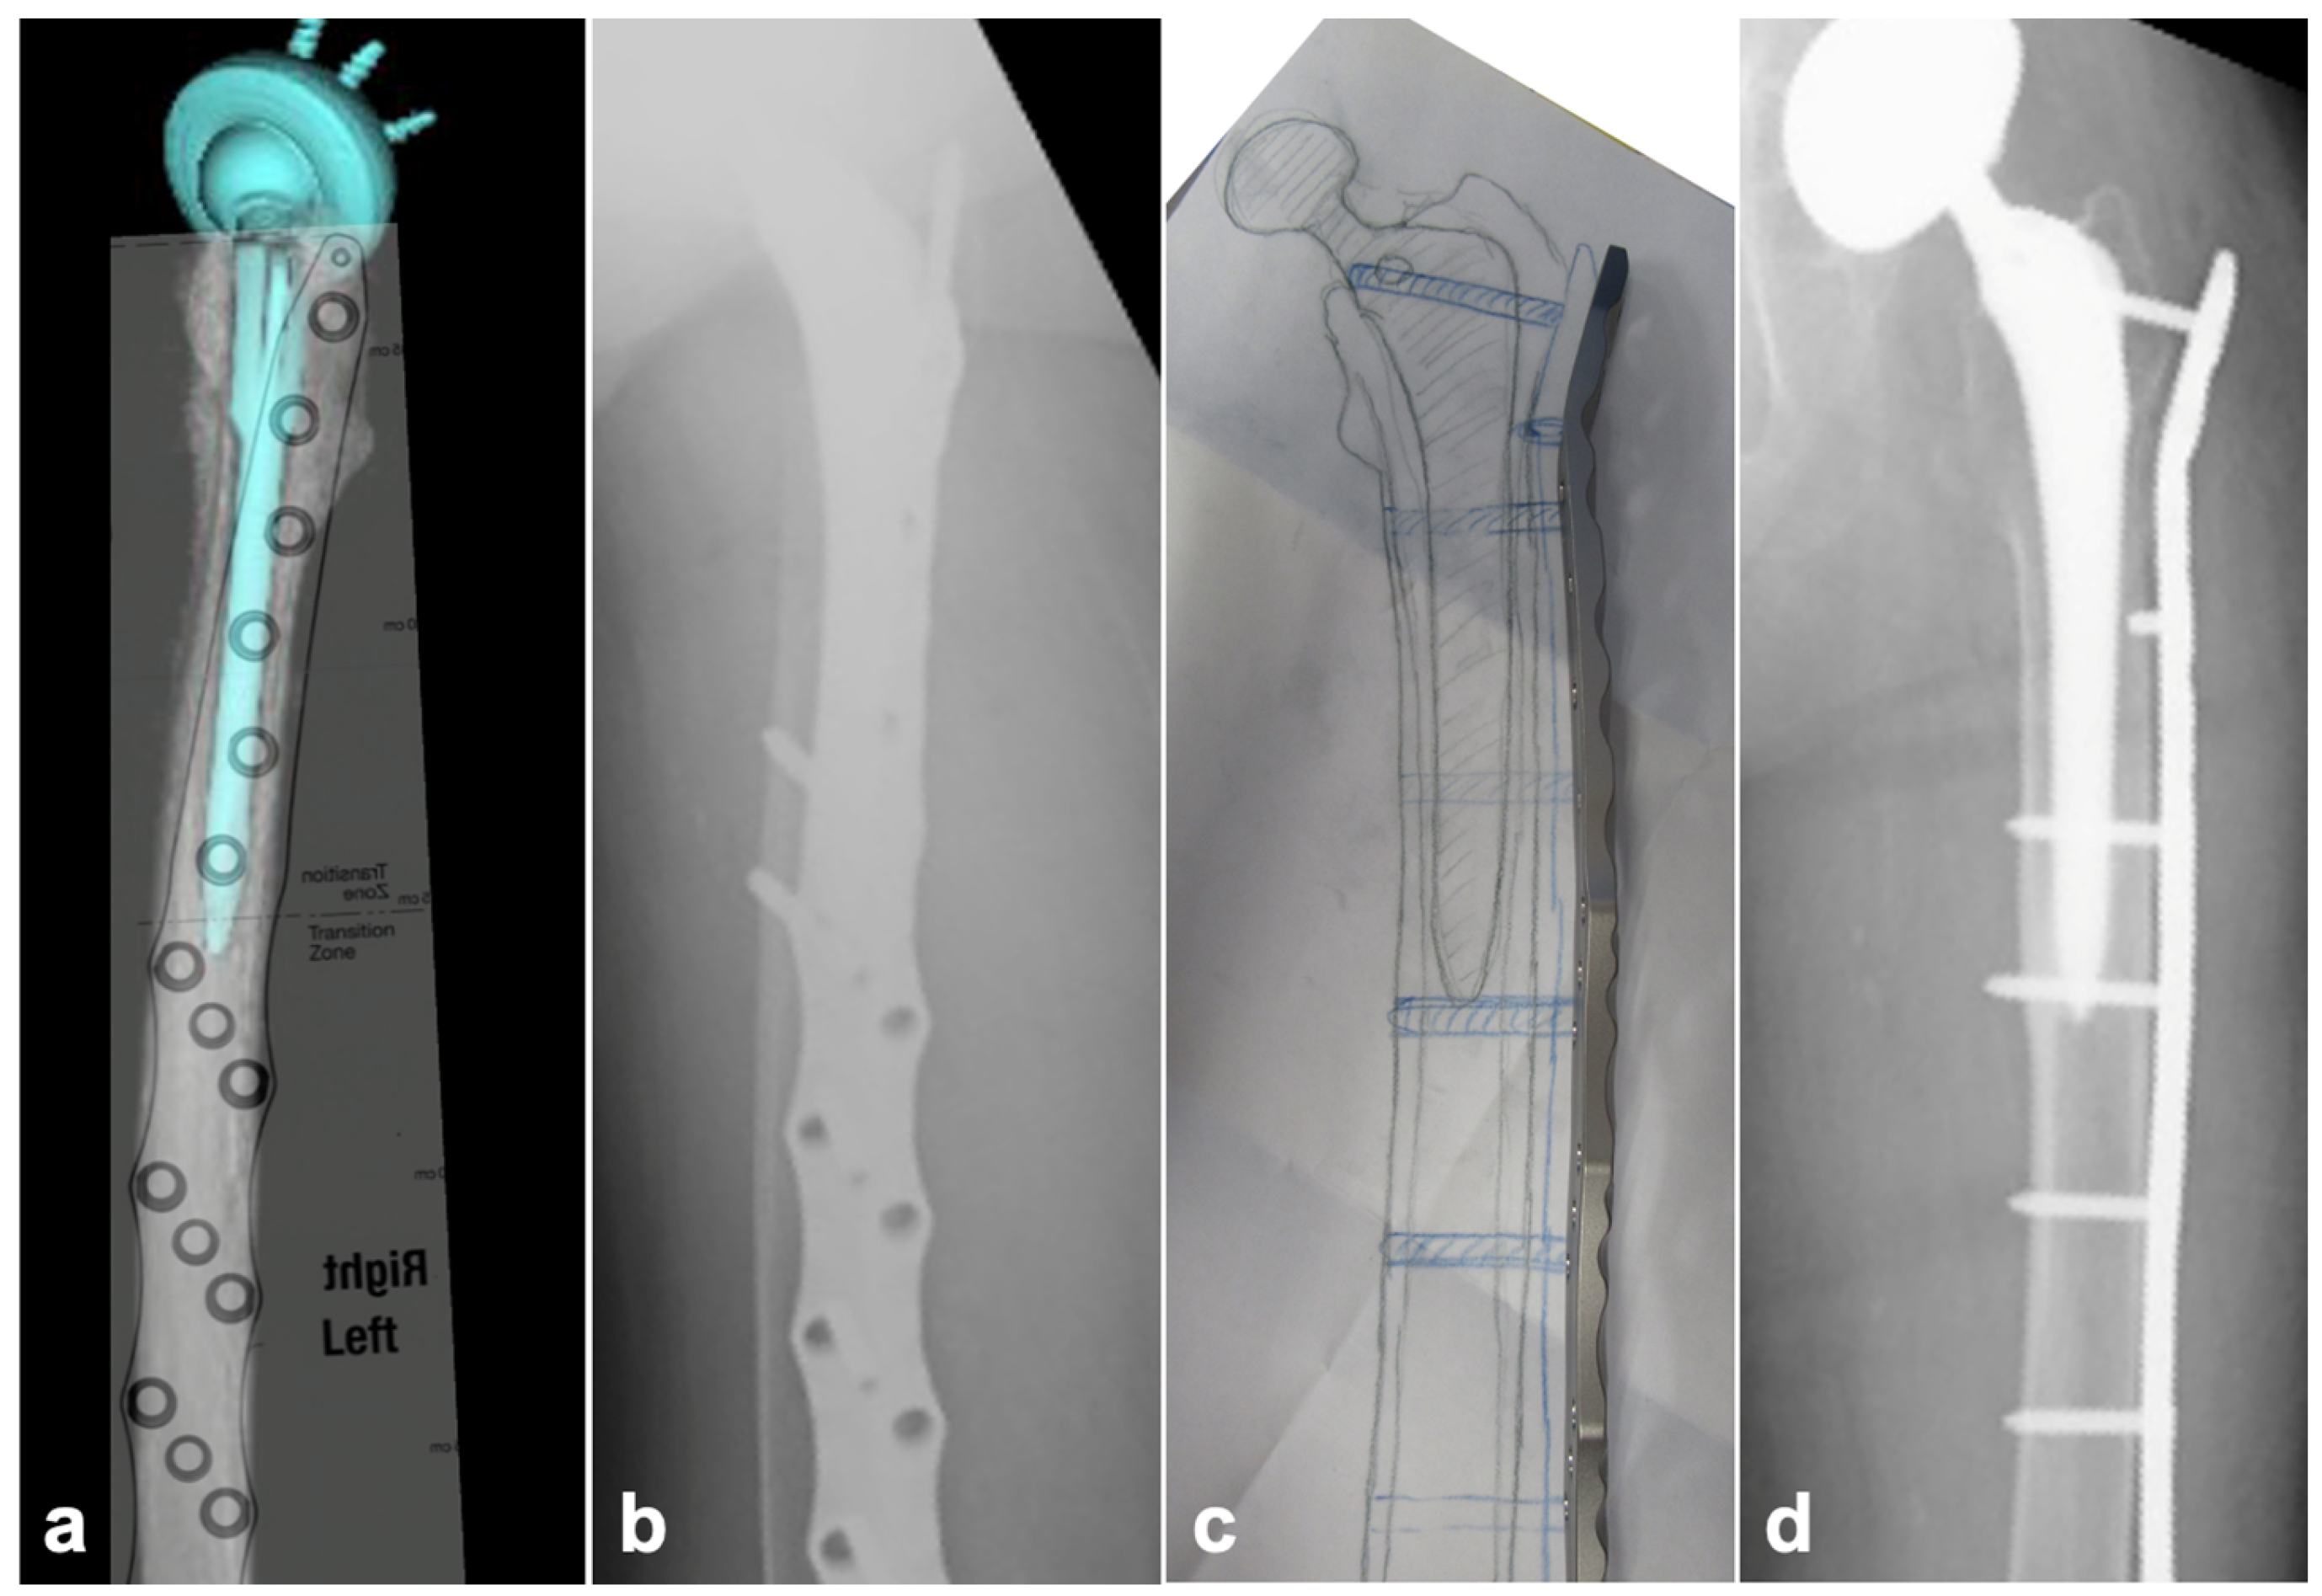

2.2. Preoperative Planning

2.3. Surgical Technique